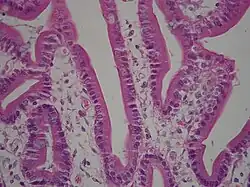

Under microscopy, the duodenum has a villous mucosa. This is distinct from the mucosa of the pylorus, which directly joins the duodenum. Like other structures of the gastrointestinal tract, the duodenum has a mucosa, submucosa, muscularis externa, and adventitia. Glands line the duodenum, known as Brunner's glands, which secrete mucus and bicarbonate in order to neutralise stomach acids. These are distinct glands not found in the ileum or jejunum, the other parts of the small intestine.[13]: 274–275

The villi of the duodenum have a leafy-looking appearance, which is a histologically identifiable structure. Brunner's glands, which secrete mucus, are only found in the duodenum. The duodenum wall consists of a very thin layer of cells that form the muscularis mucosae.